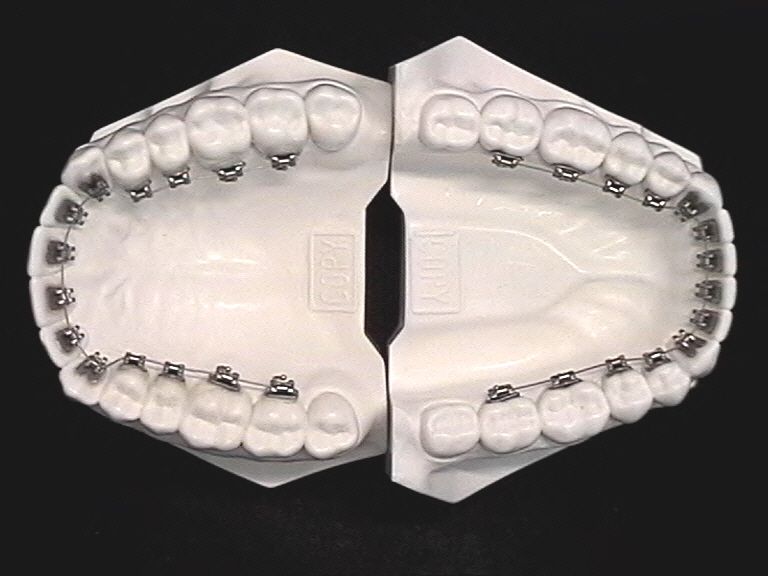

Lingualtechnik Lingualtechnik, selbsligierend

Lingualtechnik, selbsligierend

Bei der Lingualtechnik werden die Brackets auf die Innenseite der Zähne geklebt. Da die Zahnspange von außen für andere nicht sichtbar ist, ist die Lingualtechnik insbesondere für Erwachsene eine gute Behandlungsmöglichkeit.